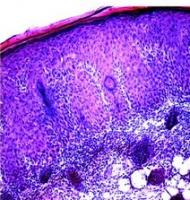

Une première preuve de concept in vitro et in vivo : la capacité des microaiguilles à pénétrer la peau a été étudiée chez des modèles animaux et sur des biopsies de peau humaine. Ces tests confirment que le médicament est efficacement administré et permet bien de réduire de manière significative la charge bactérienne.